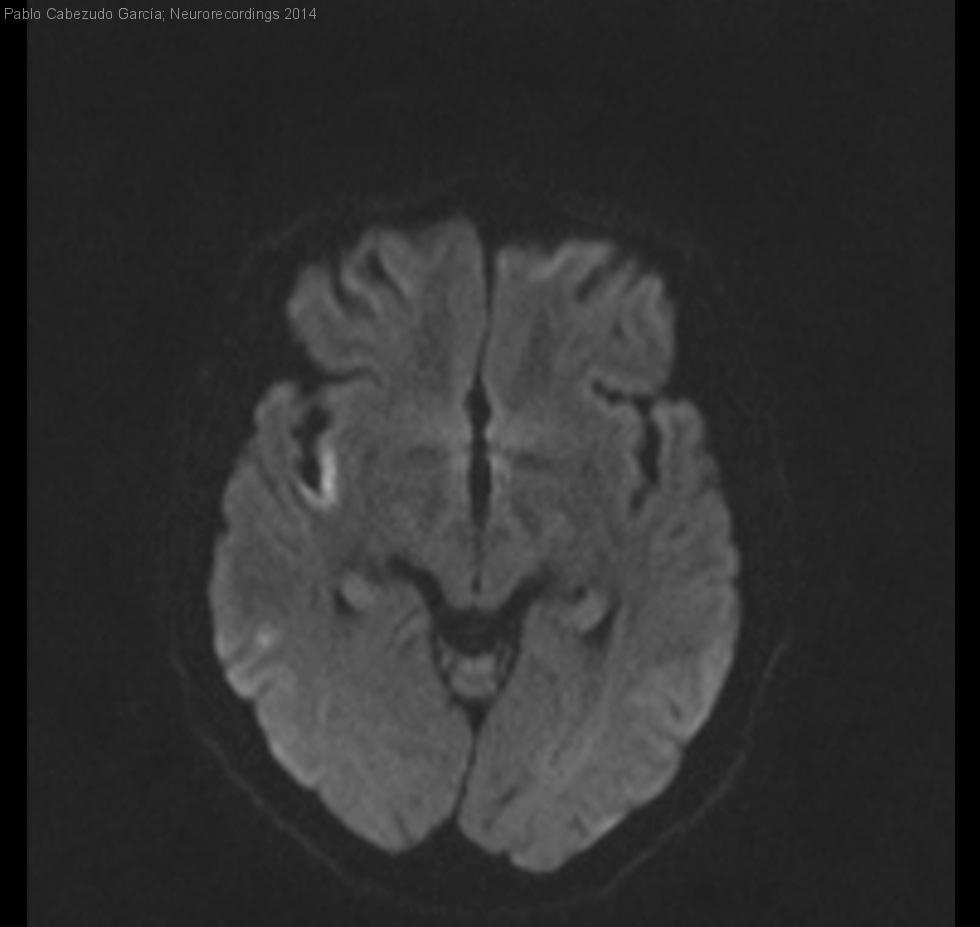

Signo del punto ("dot sign") en rama perisilviana de la arteria cerebral media.

Signo del punto ("dot sign") en rama perisilviana de la arteria cerebral media.

Diagnóstico final: Ictus isquémico criptogénico por oclusión rama perisilviana de arteria cerebral media derecha